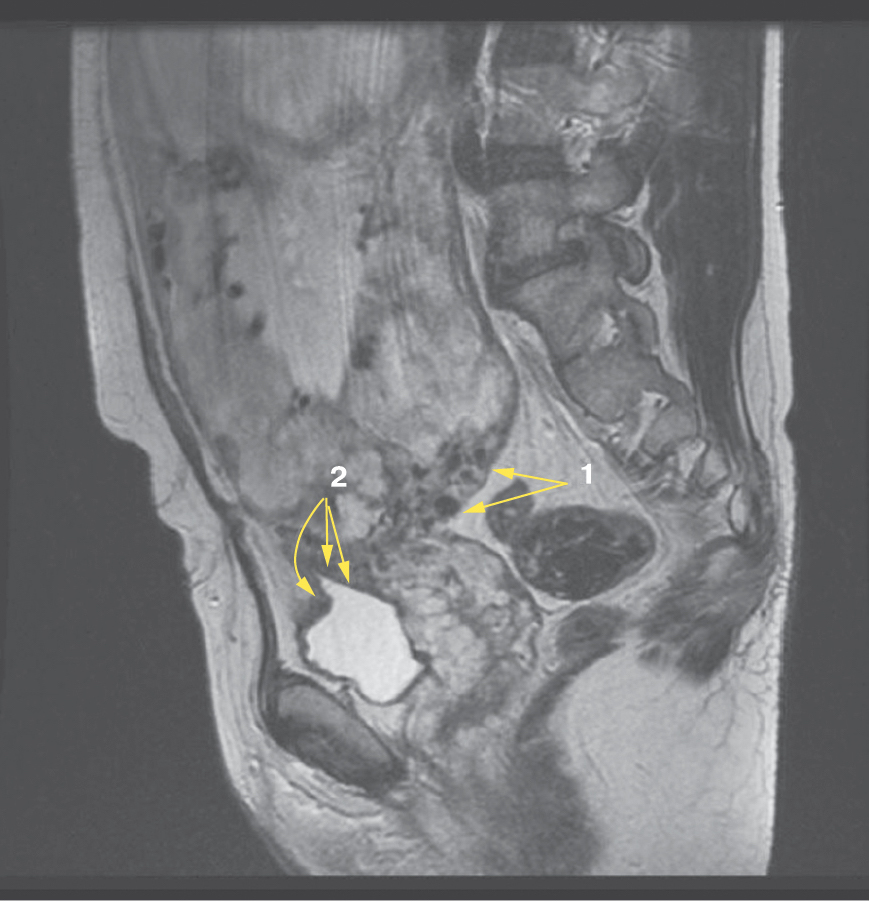

Является ли симптом «обнаженного сосуда» патогномоничным для параметральной инвазии или нет, еще предстоит выяснить; однако в ходе исследования установлена его связь с частотой гистерэктомий в группах с наличием симптома «обнаженного сосуда», что, вероятно, обусловлено мощной сосудистой сетью коллатералей и неоангиогенезом. Во всех случаях обнаружения данного признака впоследствии была выполнена вынужденная гистерэктомия (рис. 3–6, пациентка Н., 37 лет).

Рис. 3. Макропрепарат плаценты при врастании в параметрий (стрелками указаны мощные сосудистые структуры)

Рис. 4. Макропрепарат матки с врастанием плаценты в параметрий (стрелками указаны мощные сосудистые структуры)

Рис. 5. Корональная проекция МРТ. 1 – интрамуральная гиперваскуляризация; 2- измененный контур мочевого пузыря

Рис. 6. Корональная проекция МРТ. 1 – обнаженный сосуд; 2 – интрамуральная гиперваскуляризация; 3 – гиперваскуляризация плаценты